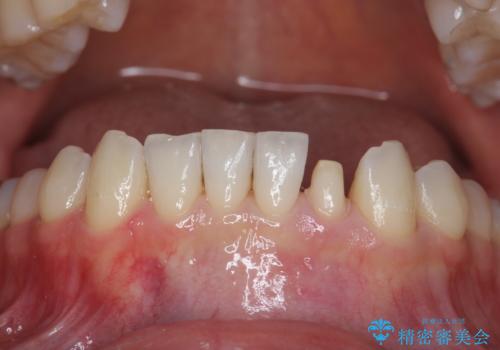

下の前歯が欠けている セラミックで審美的に エアフローで着色除去も

- 左下の前歯が削れて欠けているとのことで、治療希望されました。

プラスチックで詰めたものが度々取れてしまうとのこと。

しみないようであれば機能的にはそこまで問題はないと説明しましたが、審美的な治療をご希望でした。

プラスチックの詰め物と比較して、変色もなく、脱離もしにくいセラミッククラウンで修復しました。

前歯のステインはエアフローという方法で綺麗にクリーニングしています。

矯正治療前のかみ合わせのせいでかなり削れてしまっていたようです。その場合、矯正治療後に修復するのがおすすめです。

また、クラウンに修復するメリットとして、そのまま使っていると欠けているせいで薄い歯質がうすくなり、さらに割れてしまうリスクを防止することができます。